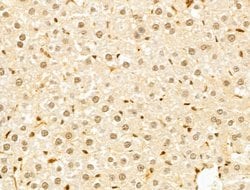

Invitrogen™ GABPB1 Polyclonal Antibody

Antibody detects endogenous levels of total GABPB1.

| Immunohistochemistry (Paraffin), Western Blot, Immunocytochemistry | |

| A synthesized peptide derived from human GABPB1(Accession Q06547), corresponding to amino acid residues V264-D314. | |

| Human, Mouse, Rat | |